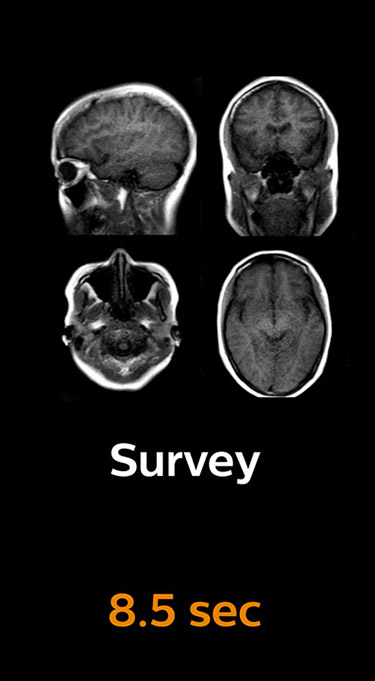

With Compressed SENSE, the scan time for the routine brain examination at KNC was reduced from 15:48 to 10:19 minutes, which corresponds to 35% reduction.

Brain with Compressed SENSE

Ingenia 3.0T CX

Scan time 10:19 min.